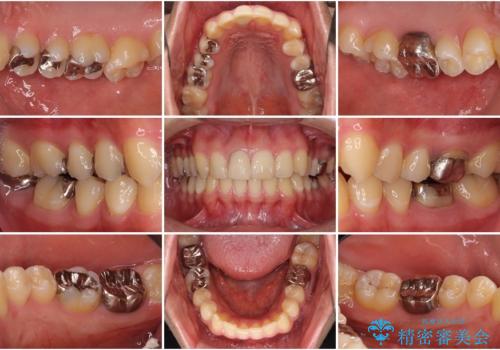

- 治療中の前歯と口腔内にある銀歯が気になるとのことで来院された患者様です。

土台に含まれている金属も含め、口腔内の金属は全て除去し、根管治療が必要な歯は根管治療を行い、オールセラミッククラウンやセラミックインレーにて治療することとしました。